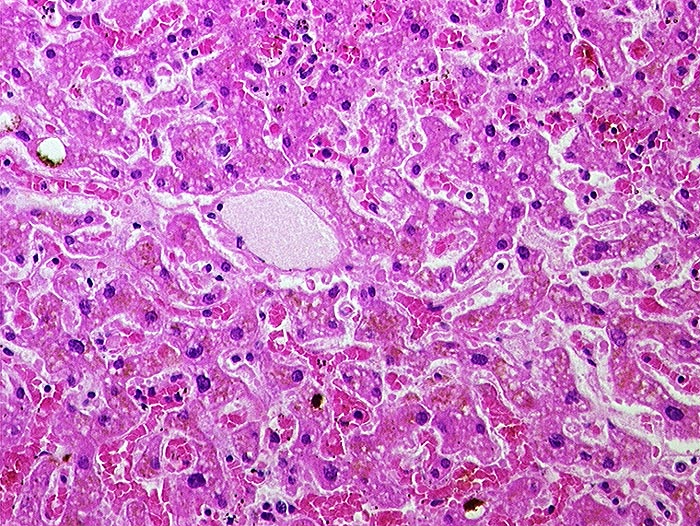

AP/ Subakute Stauung der Leber

Subakute Stauung der Leber

vaskulär / Durchblutungsstörung

Leber, Gallenwege, Pankreas

Leber

Normalbefund

Leber HE

Morphologie

Pathologischer Befund